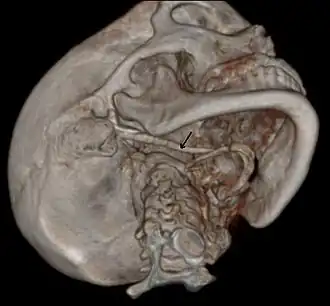

3D-reconstructed CT scan showing bilateral stylohyoid ligament ossification

Imaging is important and is diagnostic. Visualizing the styloid process on a CT scan with 3D reconstruction is the suggested imaging technique.[13] The enlarged styloid may be visible on an orthopantogram or a lateral soft tissue X ray of the neck.